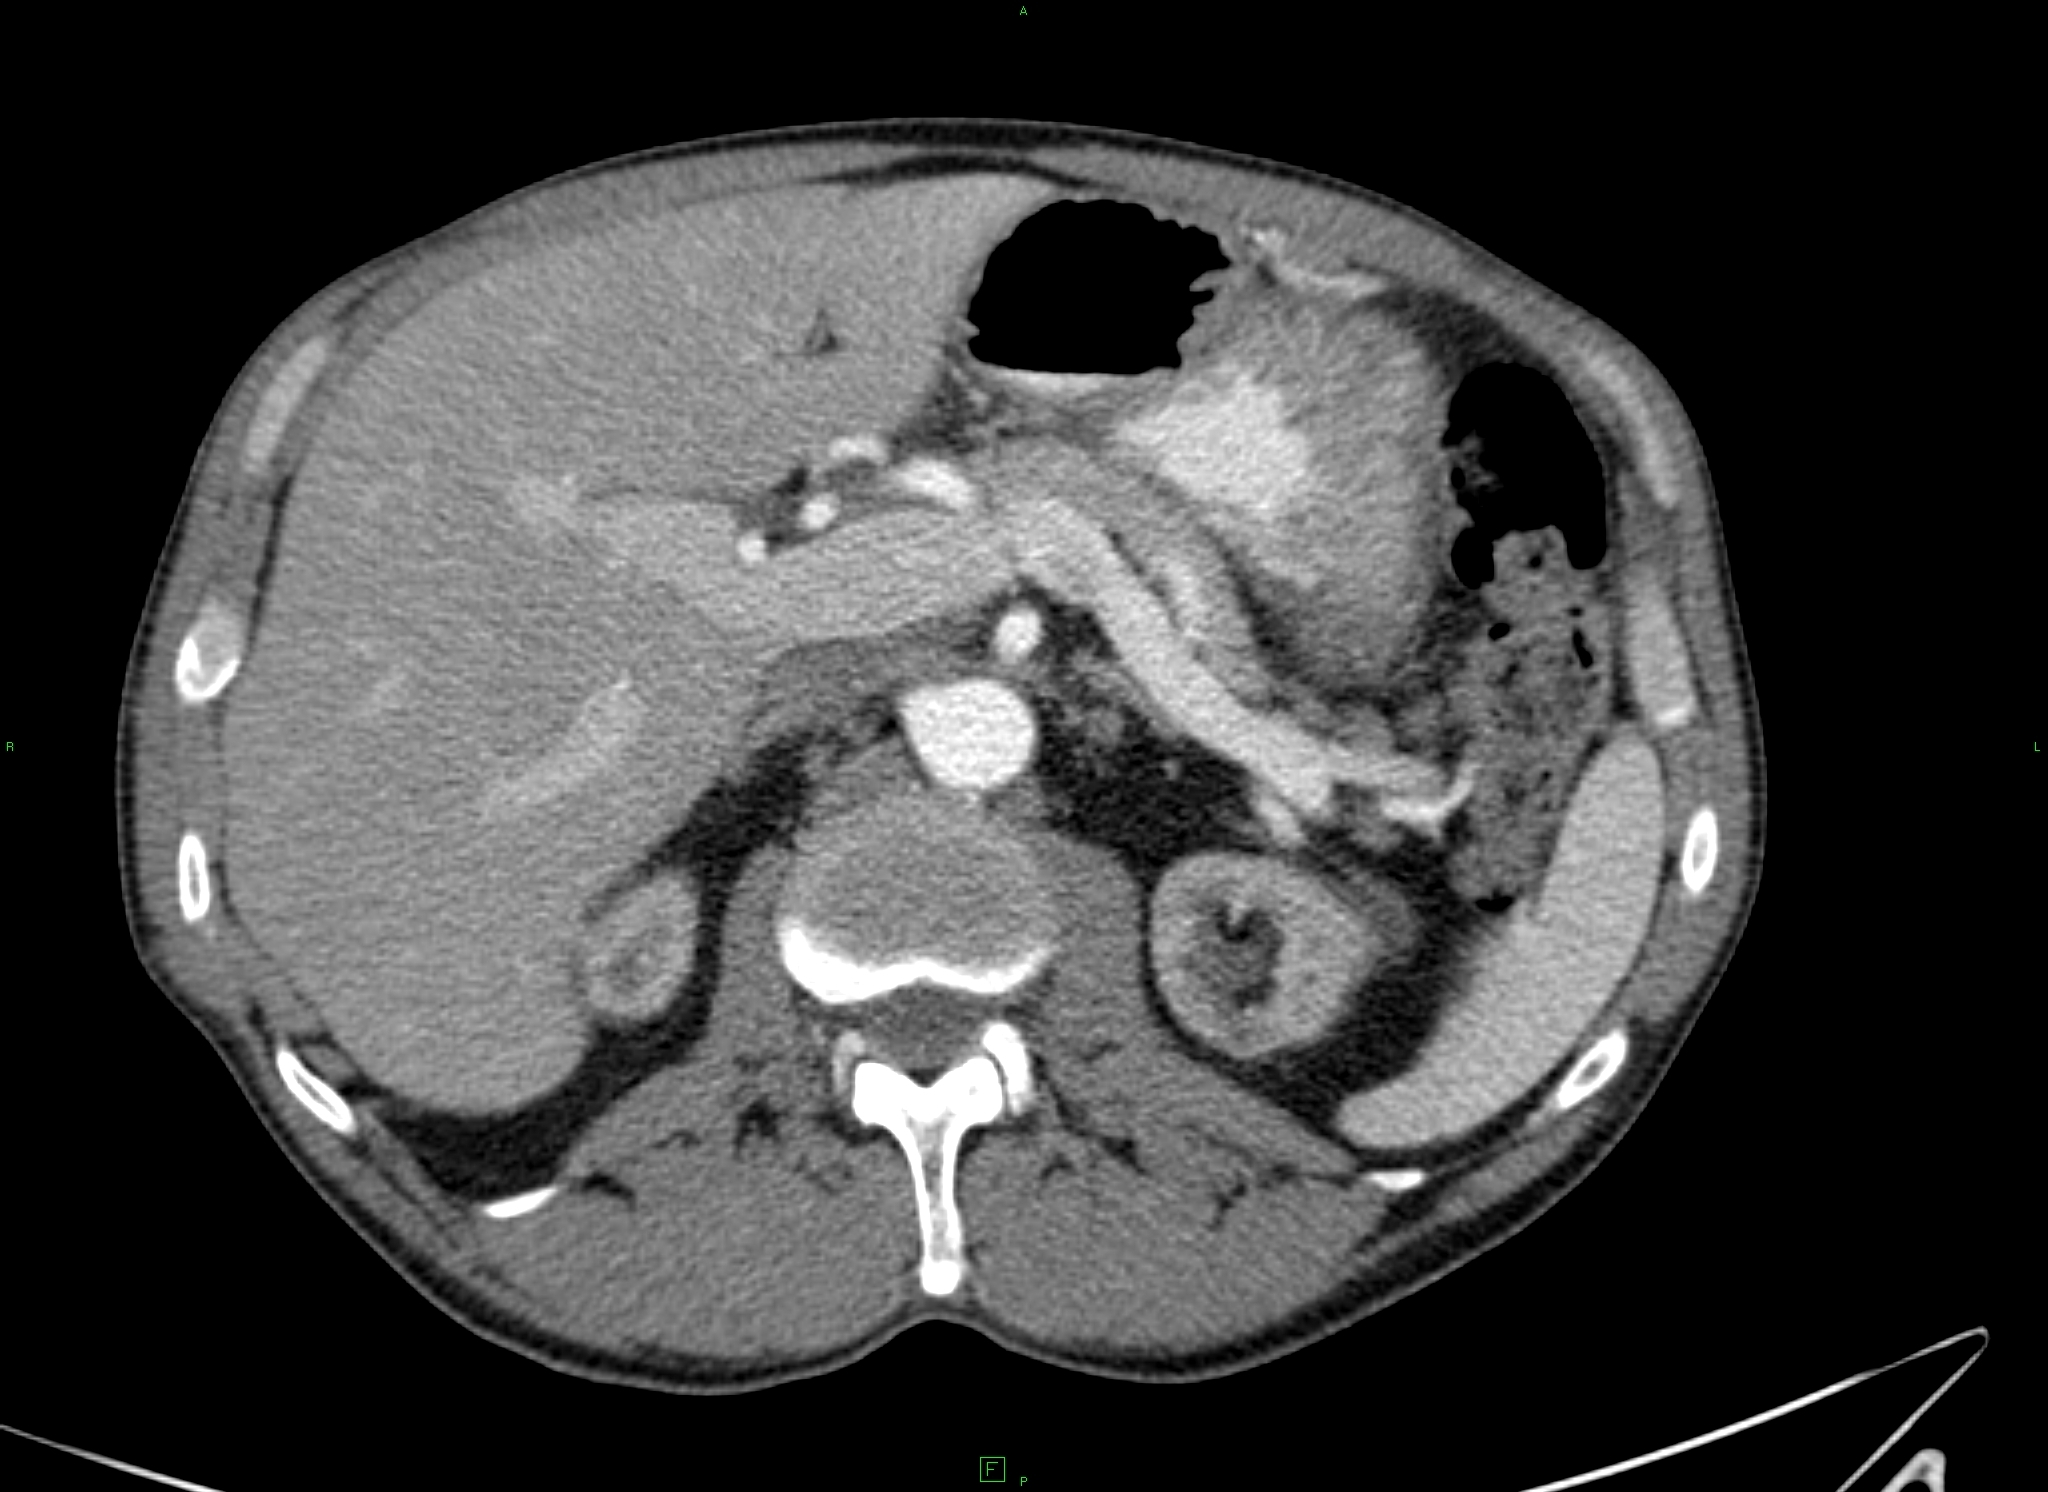

CT is the most important imaging method in case of pancreatitis.

Because of the exact diagnosis and the staging CT has a crucial importance.

CT classification of the pancreatitis according to Balthazar:

Stage A (0) - normal pancreas

Stage B (1) - focal or diffuse pancreas enlargement (Figure 39)

Stage C (2) - gland structure swelling with peripancreatic inflammatory signs

Stage D (3) - pancreatogeneous fluid content in one localisation (Figure 40)

Stage E (4) - two or more fluid content and/or gas content in the pancreas or in the adjacent area (Figure 41)

Figure 39: Acute pancreatitis, native CT, diffuse early enlargement

Figure 40: Acute pancreatitis, contrast enhanced CT, fluid in front of the body and the tail